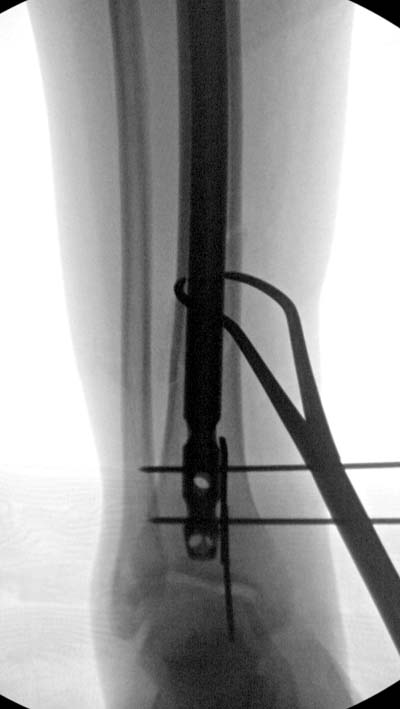

Разбор любого случая кому-то поможет лучше ориентироваться в решении вопросов, потому что в нашей работе встречаются разные связанные и несвязанные с мастерством хирурга ситуации. Возможно, отсутствие полного набора гвоздей повлияло на выбор короткого имплантата, имеется угловая и ротационная деформации. Независимо от локализации, стабильность создается, когда гвоздь проксимально не глубже 1.5 см (облегчает удаление) и дистально доходит до epiphyseal scar.

Кроме этого, имеет значение предварительная репозиция и риминг в центре канала. Интактная малоберцовая иногда затрудняет репозицию, но существуют разные приемы, нп. при застарелом можно применить дистракторы: стержневой или кольца Илизарова, а при свежих - перкутанно Weber clamp.

Мнение о том, что гвоздь сделает репозицию не всегда соответствует истине. Снимки показывают на неудачную попытку исправить направление гвоздя с помощью “поллеров”. Прием возможен только тогда, когда проход риминга в центре канала, иначе толкать гвоздь некуда.

Здесь несколько снимков изолированного перелома большеберцовой с интактной малоберцовой. Weber clamp, блокирующие спицы и риминг в центре канала отрепонировал перелом....